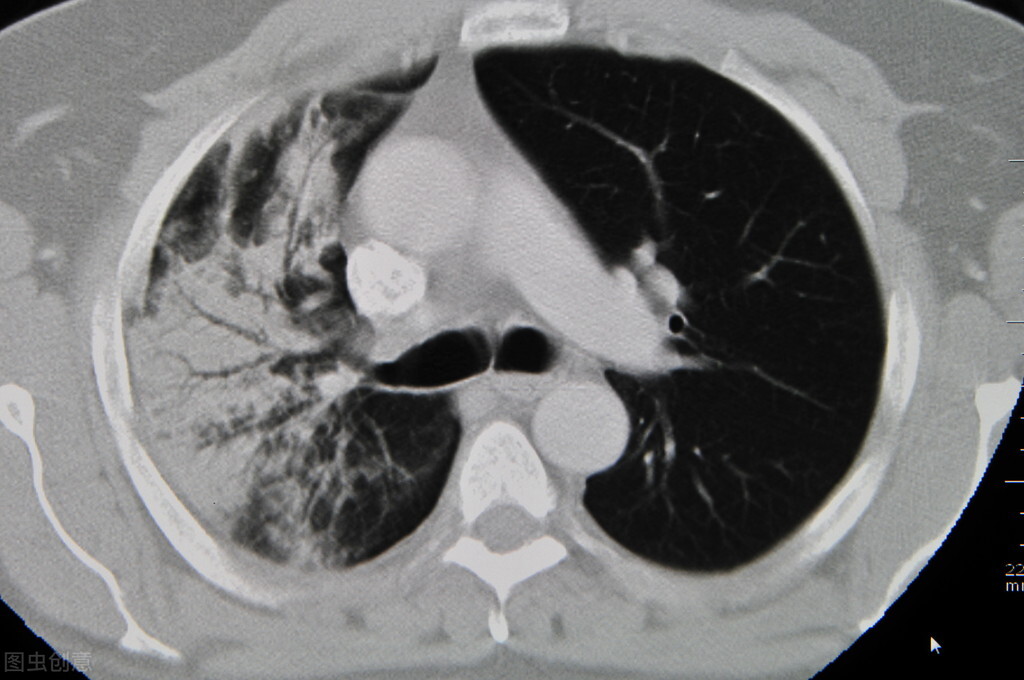

在2021年经检查发现:

1. 右肺下叶磨玻璃密度结节,倾向为早期肺癌,大小约8*8mm.

2. 右肺上叶及左肺下叶磨玻璃密度影,需警惕不典型腺瘤样增生可能,大者约0.6cm

3. 双肺另见多发小结节,倾向良性,大者约0.4cm

患者再次复查,肺上的结节缩小一半,并且磨玻璃消失不见,有效地抑制了恶变的倾向,但是对于患者来说需要进行长期调理才能更好的改善内环境,改善体质规避癌症。